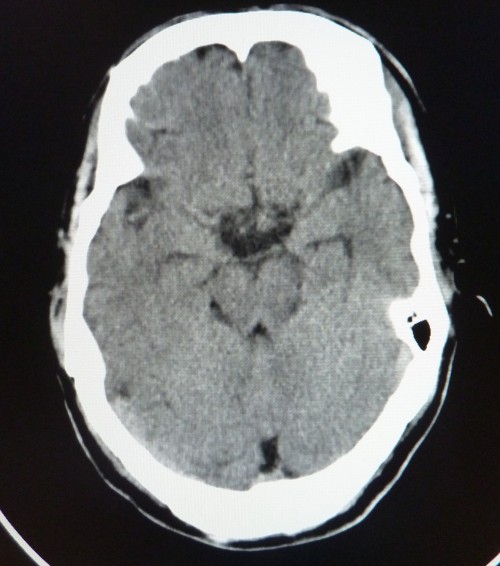

标题: CT26504:男,45岁,头痛伴呕吐两星期。 [打印本页]

标题: CT26504:男,45岁,头痛伴呕吐两星期。

鞍内可见高密度类圆形影,鞍背骨质吸收,支持垂体瘤伴出血,建议mri检查。

垂体增大,密度明显增高,考虑垂体瘤卒中,建议mr